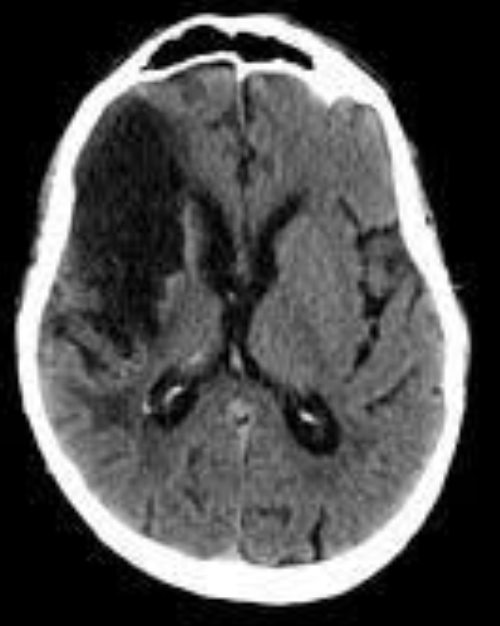

EVC hemorragico

Hipertensivo